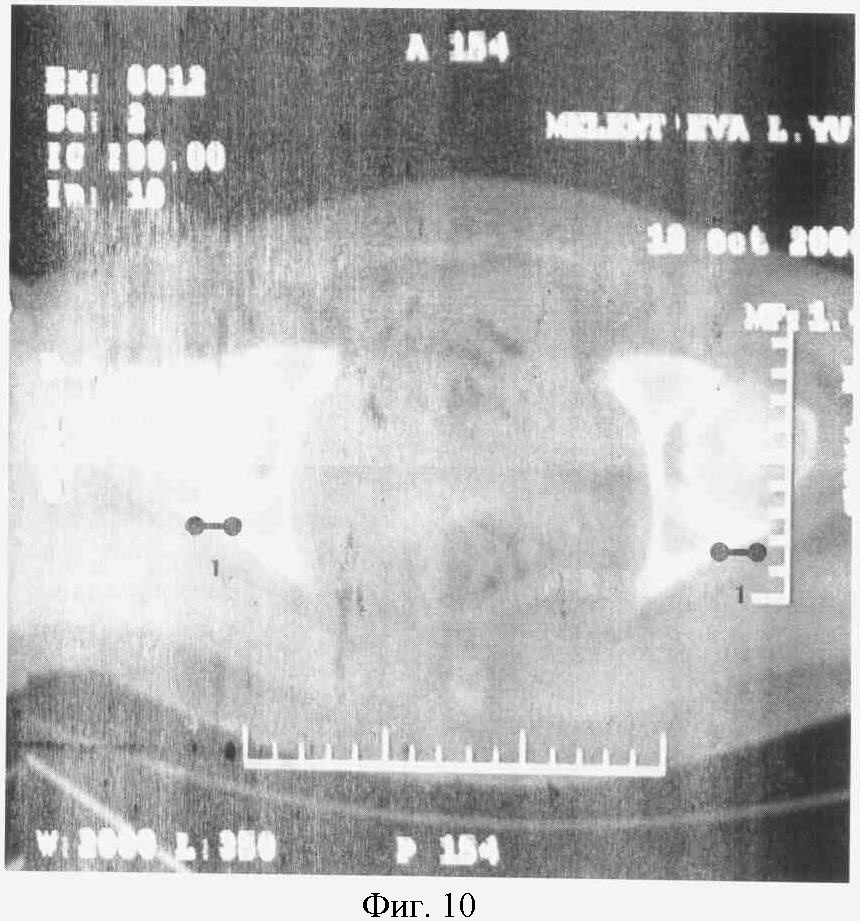

На фиг.10. представлен КТ срез на уровне средней трети (ямки) головки бедра больной М.

Справа: 2-я стадия коксартроза с локализацией участков компрессии в заднем отделе сустава (1).

Слева: 2-я стадия коксартроза с локализацией участков компрессии в заднем отделе сустава (1).

При анализе КТ срезов (фиг.9, 10, 11) от 18.10.06 г. на уровне верхней трети, уровне ямки (средней трети) головки и нижней трети было выявлено, что суставная щель на всех трех уровнях была неравномерной, имелись локальные участки компрессии в виде сужения суставной щели, локализующееся в заднем или переднем отделах сустава в виде наличия зеркально расположенных (друг против друга) ограниченных участков суставной поверхности вертлужной впадины и головки бедренной кости, с выраженным субхондральным склерозом замыкательной пластины и неровностью суставной поверхности вертлужной впадины и головки бедренной кости, с легким уплощением контура головки на данном участке, образование краевых остеофитов заднего края вертлужной впадины соответственно расположения участков сужения суставной щели, наличие компенсаторного краевого остеофита головки бедренной кости в месте ограниченного сужения суставной щели.

Диагноз после КТ исследования: Двусторонний идиопатический коксартроз. Левосторонний коксартроз 2-й стадии, декомпенсированная форма, задний выраженный компрессионный синдром, НФС 3-й степени. Правосторонний коксартроз 2-й стадии, субкомпенсированная форма, умеренный задний компрессионный синдром, НФС 2-й степени.